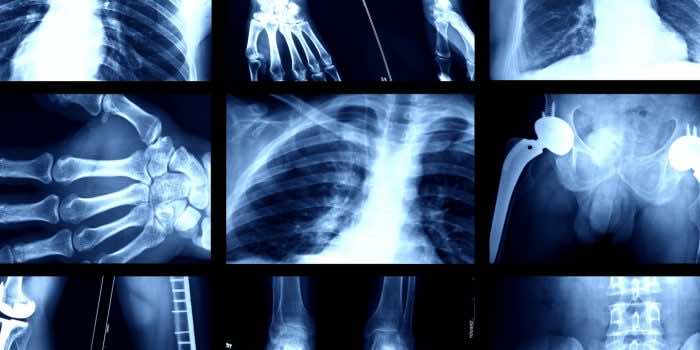

人工智能的深度学习模型现在能够从X射线射击中识别某人的种族。

“我们表明,可以培训标准的AI深度学习模型,以预测各种成像方式高性能的医学图像,这在外部验证条件下得到了维持。”

研究人员写道:“我们的发现,即AI可以准确地预测自我报告的种族,即使是从损坏,裁剪和噪音的医学图像中,通常是在临床专家无法进行的,这会给所有模型部署中的所有模型部署带来巨大的风险。”